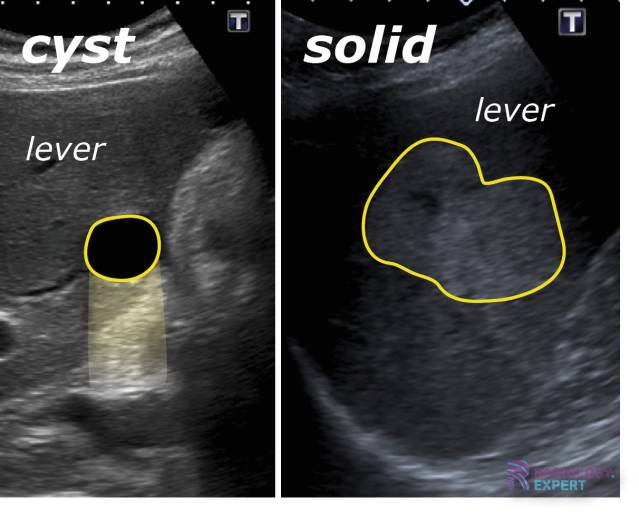

Laten we beginnen met de cyste. Een cyste is eigenlijk een zakje gevuld met vocht, lucht of ander materiaal. Je kunt het zien als een soort ballonnetje dat ergens in je lichaam ontstaat. Cysten kunnen overal voorkomen: op de huid, in organen, of zelfs in botten. Vaak zijn ze klein en onschuldig, en merk je er niet eens iets van. Andere keren kunnen ze groter worden en ongemak of pijn veroorzaken.

- Echografie: Om een beeld te krijgen van de structuur van de knobbel.

- Gebruik visuele hulpmiddelen: Zoek online naar afbeeldingen van cysten en tumoren (let op dat je geen schokkende beelden gebruikt) om het verschil te illustreren.